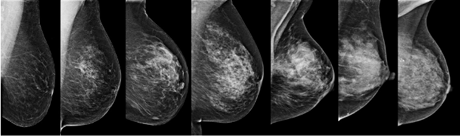

Mammography has been the accepted ‘Gold Standard’ when it comes to breast cancer screening. There is growing acknowledgement however, among researchers, that Breast Density affects the sensitivity of Mammograms.

Decades of research supports this and there is mounting global discussion as to why Breast Density is not being reported to women.

40% of women in the 45 – 55 age group have Dense Breasts. If these women were informed about this, they would be able to make an informed decision about supplemental screening, like Ultrasound and Mri.